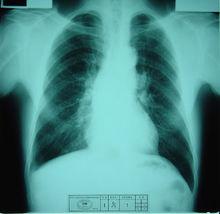

圖3肺癌合併轉移鈣化灶(圖4):右側中央型肺癌並雙肺多發轉移:右肺門可見軟組織腫塊,明顯分葉,密度不均勻,其內可見點狀鈣化灶,腫塊內可見支氣管受壓變窄,雙肺大量隨機分布大小不一類圓形結節